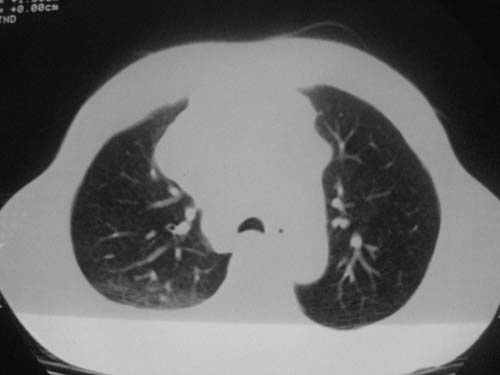

以下是引用科室第一人在2010-3-25 20:30:00的发言:[br]1:纵膈肿瘤性病变,恶性胸腺瘤可能性大伴纵膈右肺门淋巴结转移,右侧胸腔积液。[br]2:右侧肺门肿瘤性病变,纵膈淋巴结转移,右侧胸腔积液。右下叶转移。

以下是引用子期在2010-3-25 21:00:00的发言:[br]先考虑右中央型肺癌伴转移。

以下是引用江广1996在2010-3-25 22:49:00的发言:[br]通常肺癌向纵隔转移多见,纵隔肿瘤向肺内转移少见(有的表现为向肺内侵润)。本例以一元论考虑:右中心型肺癌并纵隔淋巴等多处转移。[br][br][本贴已被 江广1996 于 2010-3-25 22:50:07 修改过]

以下是引用yangyudong333在2010-3-26 6:43:00的发言:[br]“冰冻纵膈”,考虑纵膈淋巴瘤伴肺内及胸膜侵润。